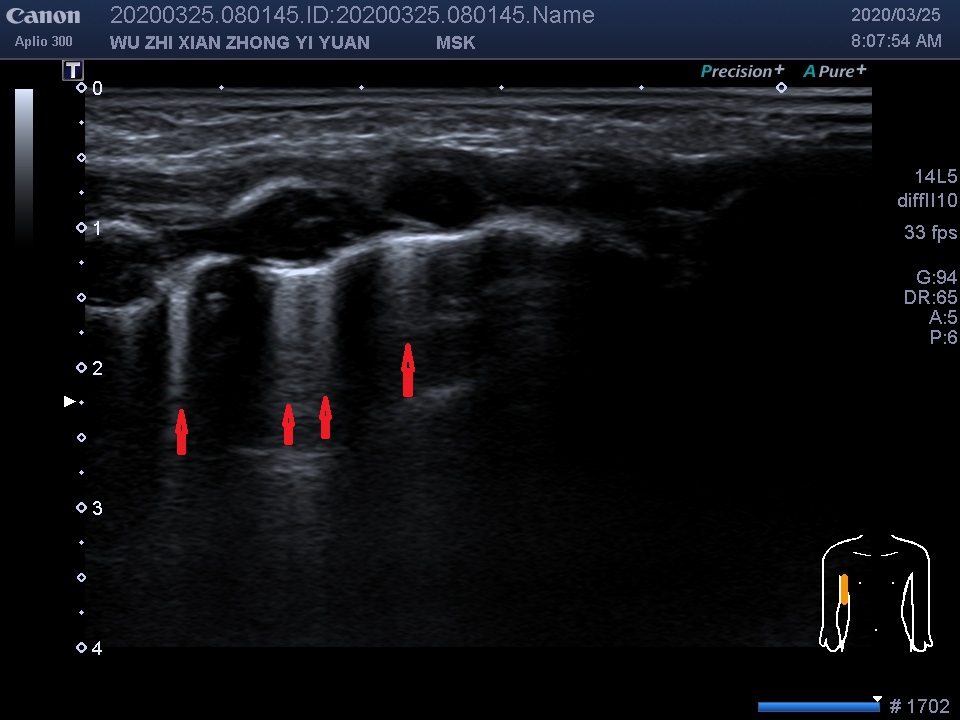

图中红色箭头所指显示:双侧背部肩胛角线及肋脊角均可见密集粗大B线。